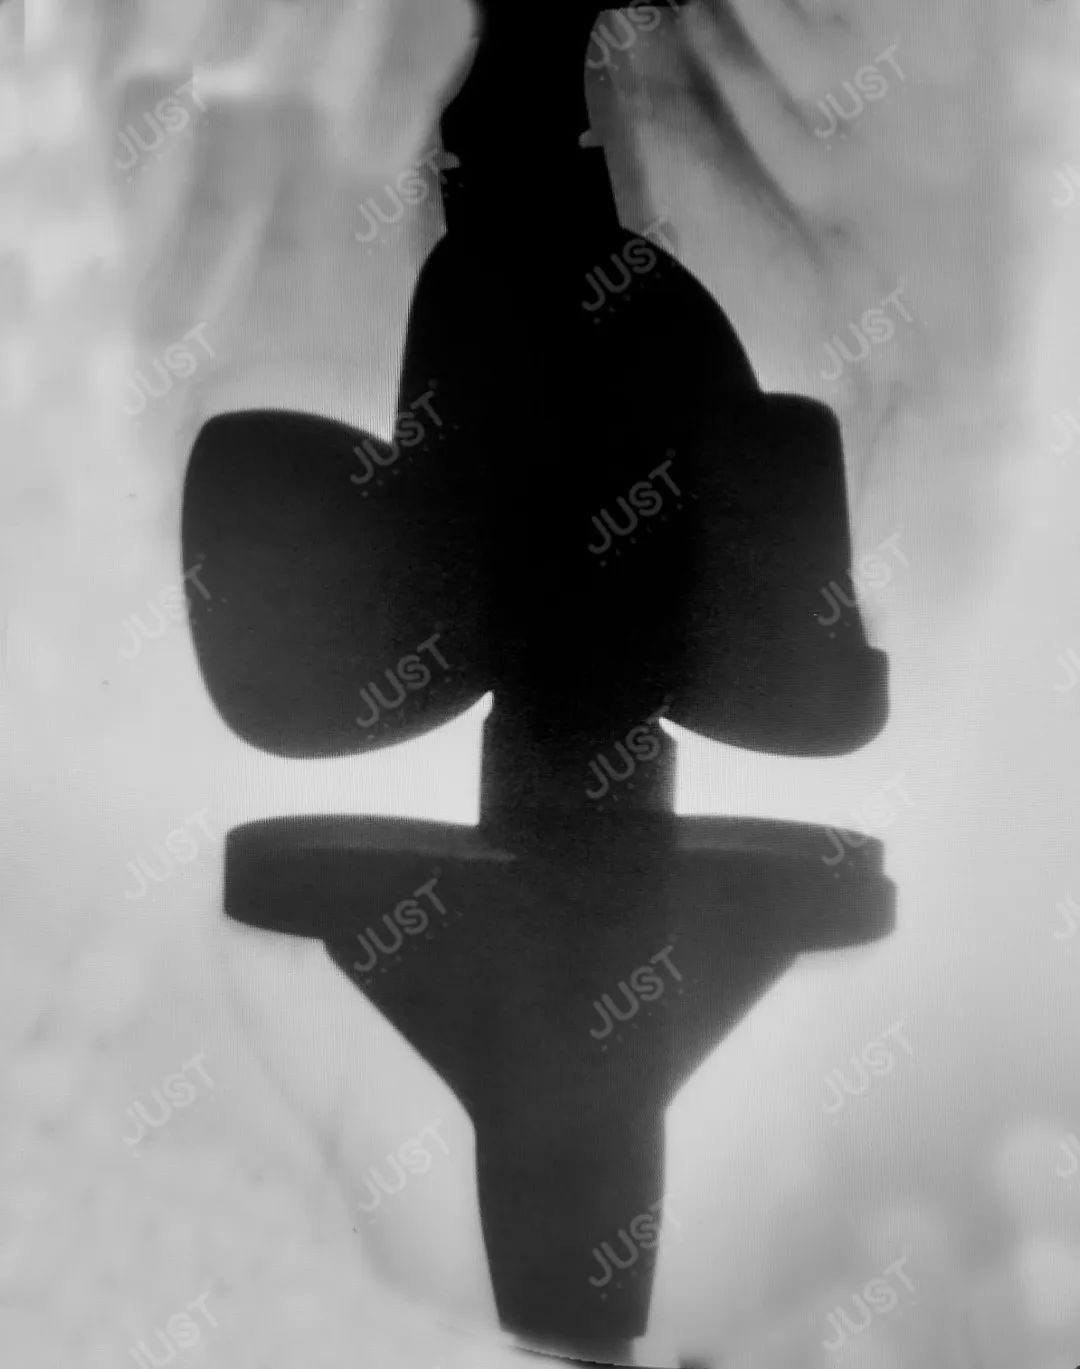

术前片